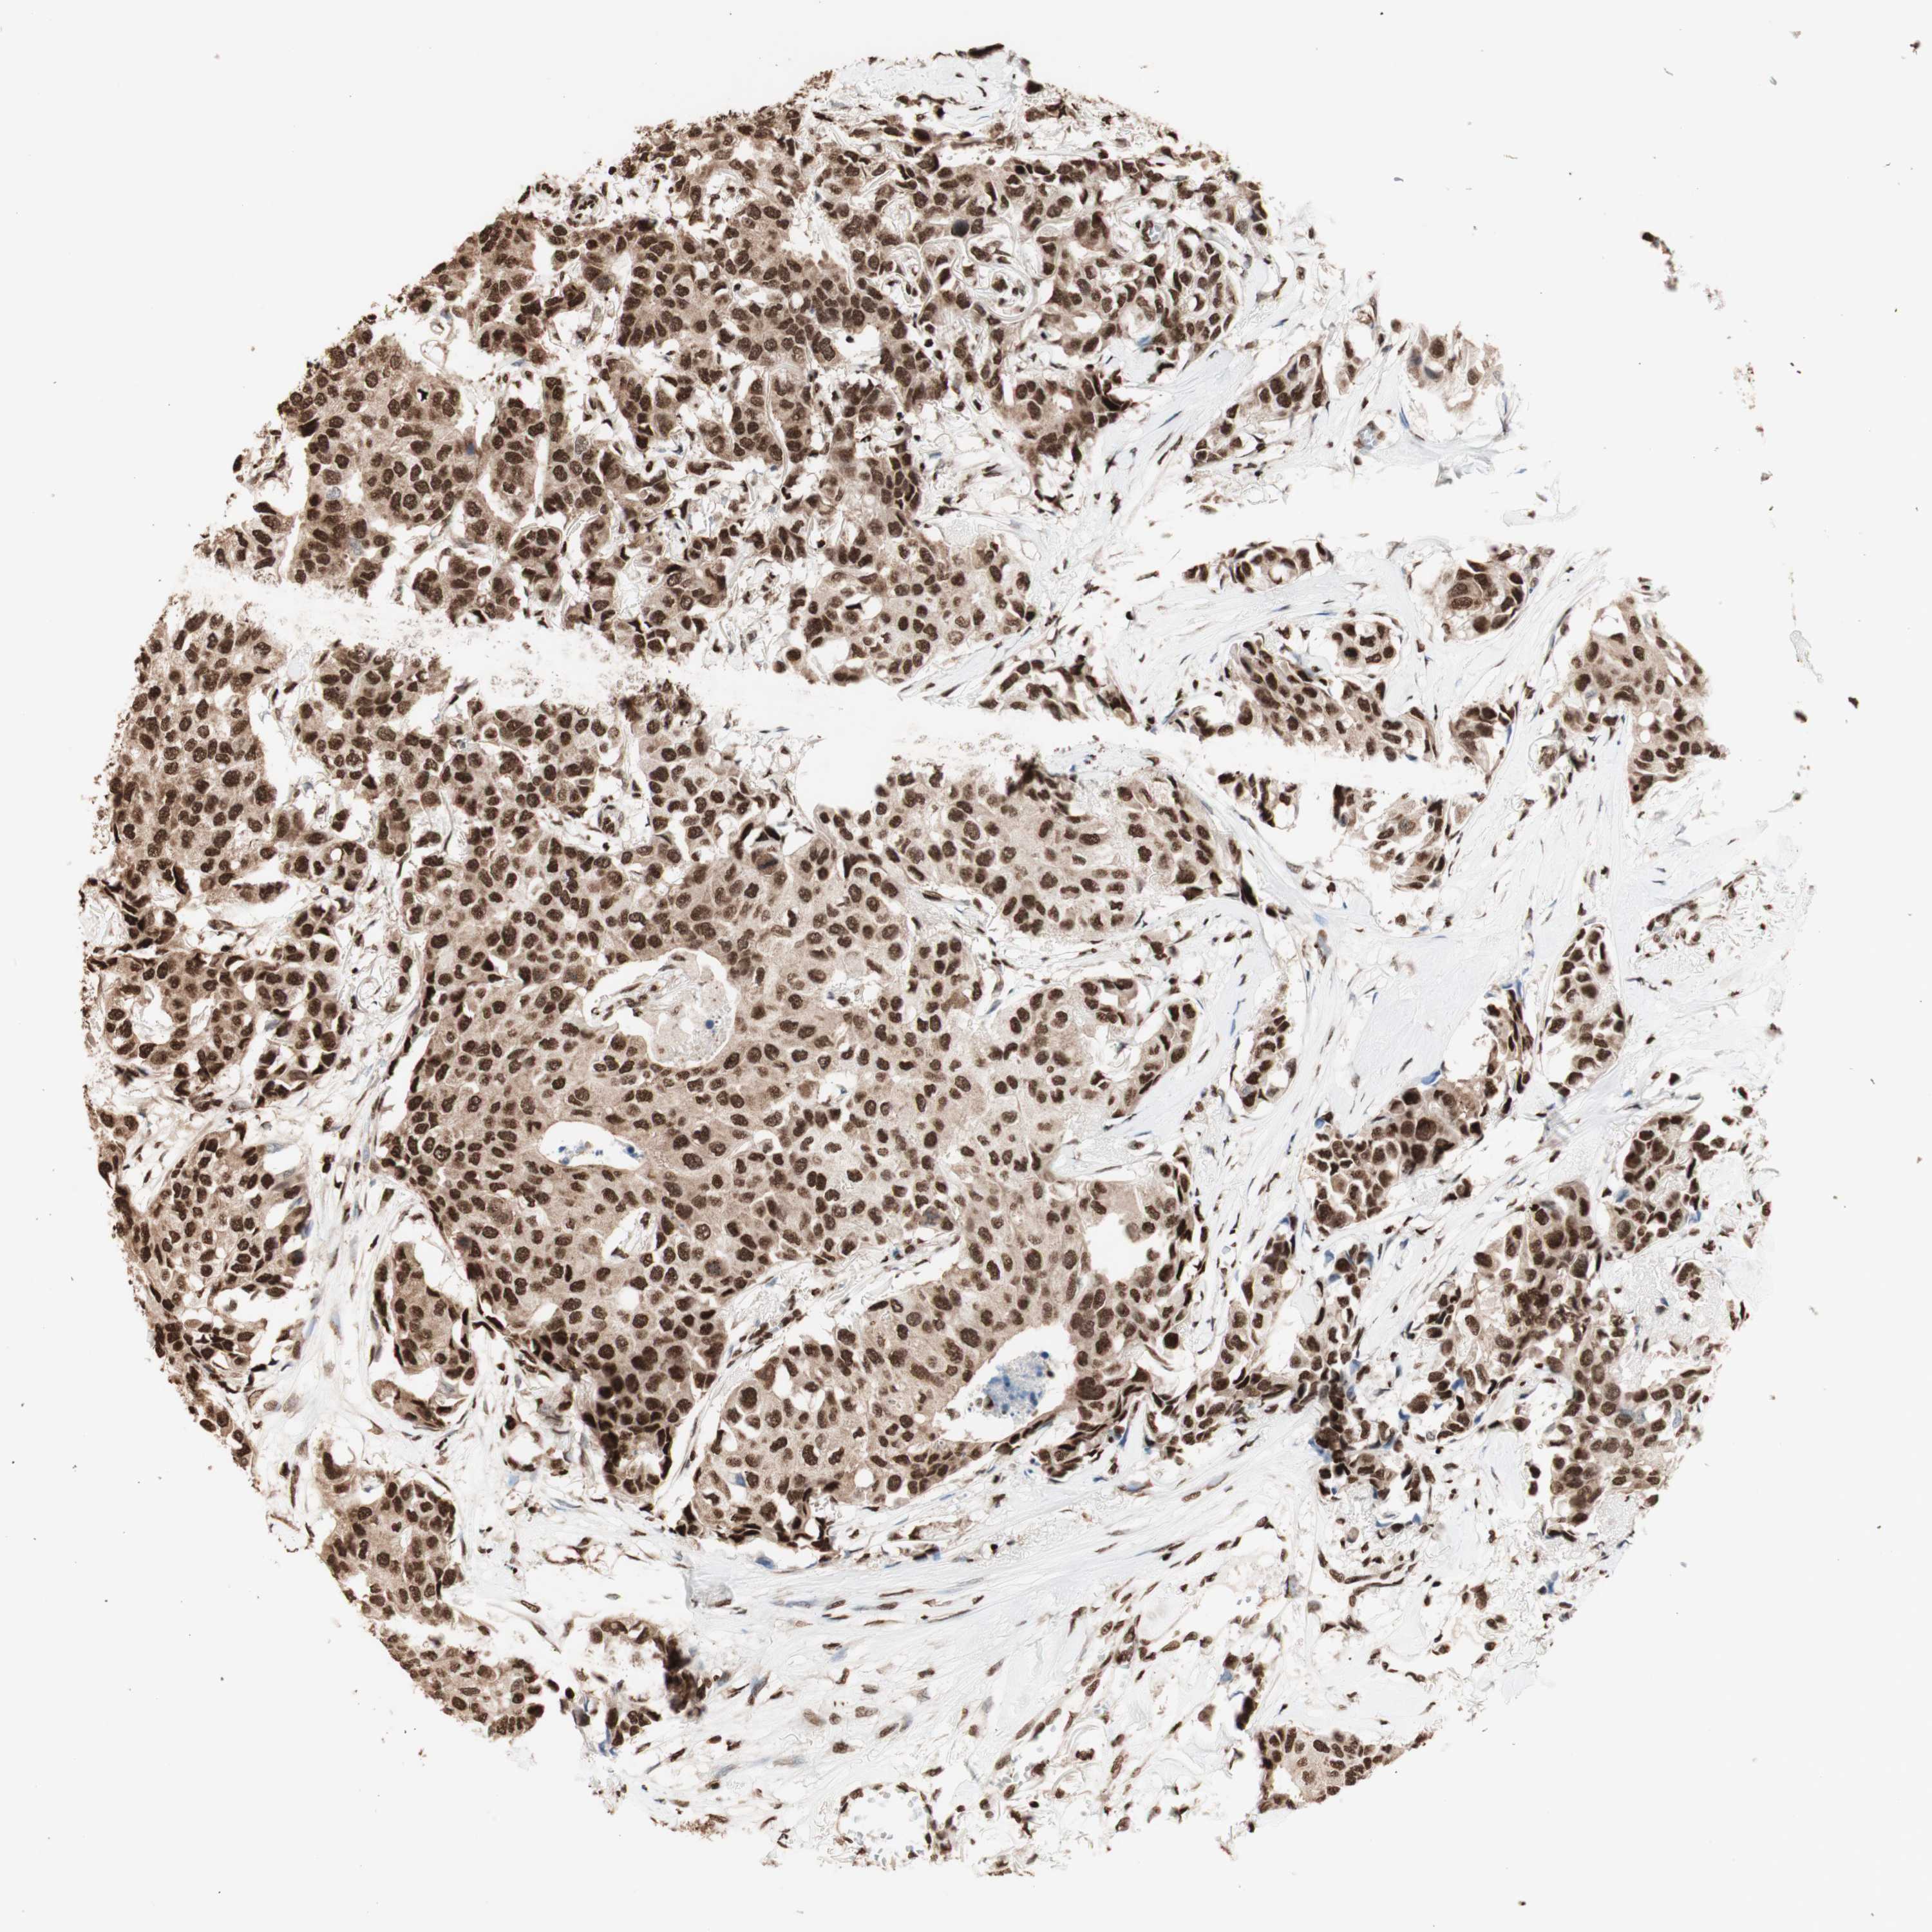

CANCER BREAST CANCER Show tissue menu

BRCA TCGA BRCA VALIDATION PROTEIN EXPRESSION